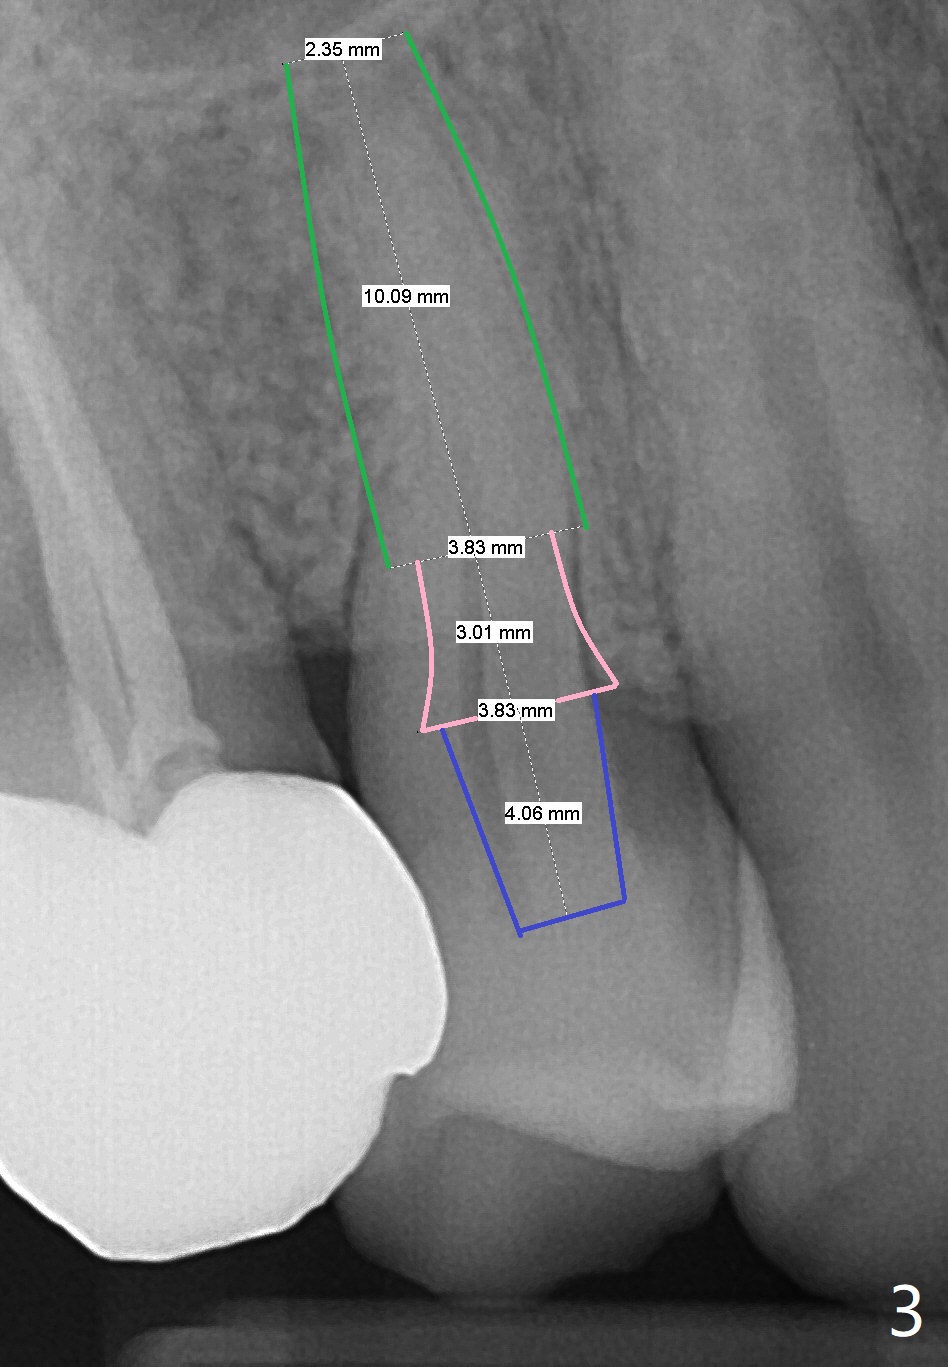

A 63-year-old man develops cold and hot sensitivity in the upper right 1st premolar after crack noise. The tooth #5 has a mesiodistal crack line (Fig.1-2). Two weeks later, the palatal cusp fractures subgingival. There is no time for guide (Fig.3). Since the root is curved and apparently difficult to extract, prepare surgical hand piece for socket shield.